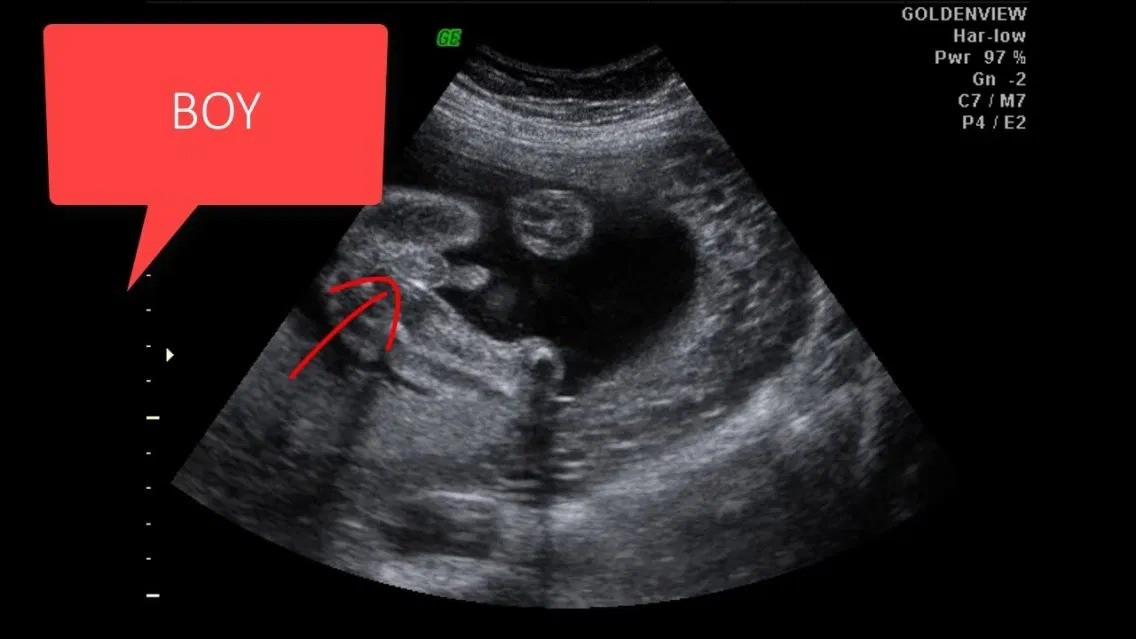

Bên cạnh việc siêu âm để theo dõi quá trình phát triển của bé, nhiều gia đình còn thực hiện siêu âm để giải đáp thắc mắc 12 tuần biết trai hay gái chưa. Nhờ sự phát triển trong cấu trúc cơ quan sinh dục với những chuyển biến rõ rệt nên hình ảnh siêu âm bé trai 12 tuần hay bé gái có thể giúp bác sĩ xác định giới tính thai nhi nhưng chưa thể chính xác hoàn toàn.

Nhịp tim không liên quan đến giới tính thai nhi. Mẹ có thể xác định giới tính thai nhi bằng siêu âm như đã viết ở trên. Tuy nhiên ở tuần thứ 12, việc xác định giới tính thai nhi chưa chính xác hoàn toàn.